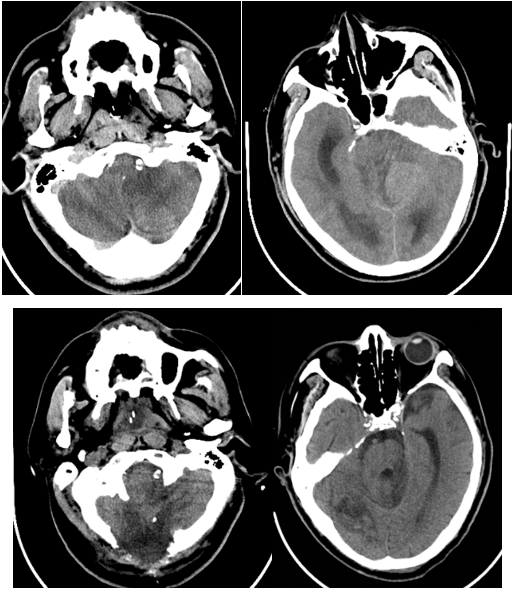

六十多岁的朱先生因“头晕19小时意识不清2小时”来到我院急诊,急诊神经科医师接诊后考虑脑血管疾病,立即行头颈部CTA+CTP检查,判断闭塞血管及梗死面积。影像科张卫国主任团体第一时间完成头颈CTA+CTP后处理,结果提示患者左侧椎动脉V1段起始处次全闭塞,右侧椎动脉V4段闭塞;基底动脉闭塞;双侧椎动脉供血区(双侧小脑、脑干、部分颞叶)缺血性灌注异常。

由于患者错过了4.5小时脑卒中静脉溶栓救治时间,无法溶栓治疗。郝永岗副主任带领神经血管介入团队评估病情后决定在全麻下为患者实施动脉取栓术,挽救处在缺血状态尚未坏死的脑组织。麻醉科李健主任第一时间到达导管室,保障手术顺利进行,术中可见患者基底动脉末端闭塞(基底动脉尖综合征)。医生运用SWIM技术取出黑红色血栓,复查造影显示:基底动脉远端血流通畅,双侧大脑后动脉、小脑上动脉显影。术中发现患者左侧椎动脉起始部重度狭窄,于病变处植入支架一枚,血管狭窄解除,术后送重症医学科继续治疗。